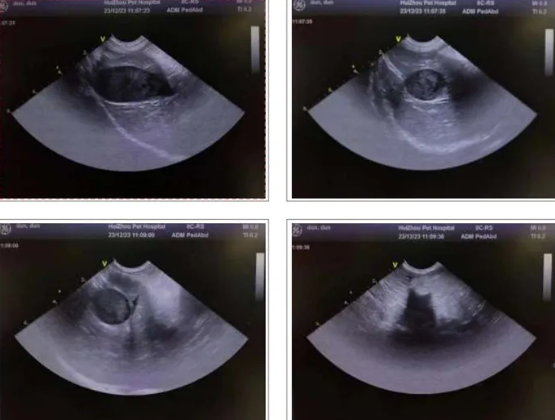

2.4 Ultrasound examination

1. The gallbladder wall is smooth, with unclear internal echoes, and no obvious dilation of the bile duct is observed.

2. The liver is normal in shape and size, with a smooth and continuous capsule, homogeneous parenchymal echogenicity, and clear intrahepatic tubular structures with normal course. Hypoechoic areas are visible in the interlobular spaces of the liver.

3. The spleen is normal in shape but enlarged in size, with homogeneous parenchymal echoes and a slightly hypoechoic mass visible within it.

4. The size and shape of the duodenal bulb, descending segment, and horizontal segment are normal, and the walls are still smooth. No definite ulcers or masses are seen in any part of the duodenum, and there are no signs of duodenal reflux.

5. Both kidneys are normal in size and shape, with smooth and regular contours, homogeneous parenchymal echoes, no space-occupying lesions, no separation of the collecting system, no dilation of either ureter, and no obvious abnormal echoes within them. The bladder is adequately filled, with smooth and continuous walls, and no obvious abnormal echoes within the cavity. A fluid-filled dark area is visible around the bladder.